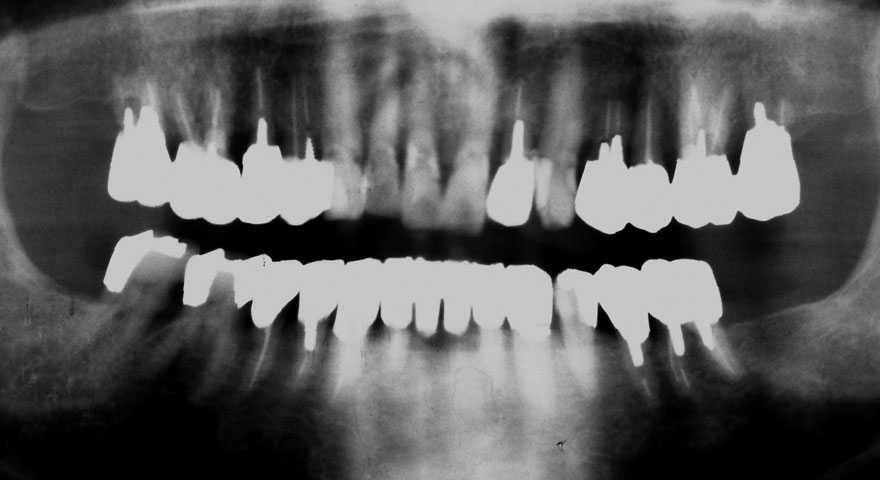

初診時 63歳 女性 平均歯槽骨喪失量:3.55mm

23年後 86歳

平均歯槽骨喪失量:3.71mm

23年間喪失量:-0.17mm

年間喪失速度:-0.007mm

(ケア頻度:1.20ヵ月ごと)